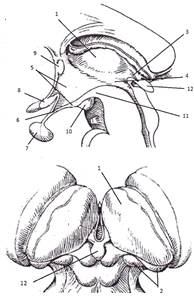

Строение сердца. Общие сведения

Сердце (cor) у человека четырехкамерное. В

сердце расположены продольные перегородки (межпредсердная -4 и межжелудочковая

– 14), которые делят орган на две изолированные половины – правое и левое

сердце, поперечная перегородка делит каждую из этих половин на верхнюю камеру –

предсердие и нижнюю – желудочек сердца.

Предсердия принимают кровь из вен и проталкивают

ее в желудочки, желудочки выбрасывают кровь в артерии. Из правого желудочка

кровь поступает в легочные артерии, а из левого желудочка – в аорту. От аорты

берут начало многочисленные артерии, идущие к органам тела. Каждое предсердие

сообщается с соответствующим желудочком через предсердно-желудочковое

отверстие. Правая половина сердца содержит венозную кровь, а левая –

артериальную кровь.

Строение правого предсердия и желудочка

Правая половина сердца содержит венозную кровь и

состоит из правого предсердия (atrium dexstrum) и правого желудочка

(ventriculus dexter). Правое предсердие имеет форму куба, располагается в

основании сердца справа и позади аорты и легочного ствола. От левого предсердия

отделяется межпредсердной перегородкой (16), на которой находится овальная ямка

(15), которая является остатком овального отверстия через которое сообщаются

между собой предсердия во внутриутробном развитии. В правое предсердие впадает

верхняя полая вена (1), нижняя полая вена (14) и венечный синус (13). Верхняя

часть правого предсердия образована правым ушком сердца (5). Правое предсердие

сообщается с правым желудочком при помощи предсердно-желудочкового отверстия.

Правый желудочек имеет форму треугольной

пирамиды, с верхушкой обращенной вниз и располагается справа и спереди от

левого желудочка. От левого желудочка отделяется при помощи межжелудочковой

перегородки. Вверху в стенке желудочка есть два отверстия: сзади – правое

предсердно-желудочковое, а спереди – отверстие легочного ствола.

Предсердно-желудочковое отверстие закрывается при помощи трехстворчатого

клапана (8). Внутри правого желудочка находятся трабекулы и сосочковые мышцы,

от которых к створкам клапана идут сухожильные хорды. Из правого желудочка

начинается легочной ствол (6). Между правым желудочком и легочным стволом

находится полулунный клапан легочного ствола.

Строение левого предсердия и желудочка

Левая половина сердца содержит артериальную

кровь и состоит из левого предсердия (atrium sinistrum) и левого желудочка

(ventriculus sinister).

Левое предсердие имеет форму неправильного куба,

отграничено от правого межпредсердной перегородкой, имеет левое ушко (15). В

левое предсердие открываются 4 легочные вены, лишенные клапанов, они приносят

артериальную кровь от дёгких. С левым желудочком сообщается с помощью

предсердно-желудочкового отверстия, возле которого находятся гребенчатые мышцы.

Левый желудочек (16) конусовидный, его основание

обращено кверху. В переднем верхнем отделе желудочек сообщается с аортой. У

места выхода аорты из левого желудочка имеется клапан аорты, который состоит из

правой, левой и задней полулунных заслонок. В предсердно-желудочковом отверстии

располагается двухстворчатый клапан (митральный – 7).

На внутренней поверхности левого желудочка

находятся мясистые трабекулы (10) и две сосочковые мышцы (9), от которых идут

сухожильные хорды (8), прикрепляющиеся к свободным краям створок митрального

клапана.

Толщина стенок левого предсердия около 2 мм, а

желудочка – до 15 мм. Верхушку сердца полностью выполняет левый желудочек.

Строение перикарда, проводящая система сердца

Мускулатура предсердий и желудочков

функционально соединяется друг с другом при помощи проводящей системы сердца,

представляющей собой сложное нервно-мышечное образование. Проводящие волокна,

входящие в ее состав имеют особое строение: их клетки бедны миофибриллами, но

богаты саркоплазмой. В проводящей системе различают узлы и пучки: 1.

Синусно-предсердный узел (1) расположен в стенке правого предсердия. Он связан

с мускулатурой предсердий и обеспечивает их ритмическое сокращение. 2.

Предсердно-желудочковый узел расположен в стенке правого предсердия вблизи

трехстворчатого клапана (2). 3. Предсердно-желудочковый пучок (пучок Гисса – 3)

находится в перегородке между предсердиями и желудочками. 4. Ножки пучка Гисса

(4) находятся в мускулатуре желудочков. 5. Волокна Пуркинье (5) ветвятся под

эндокардом желудочков.